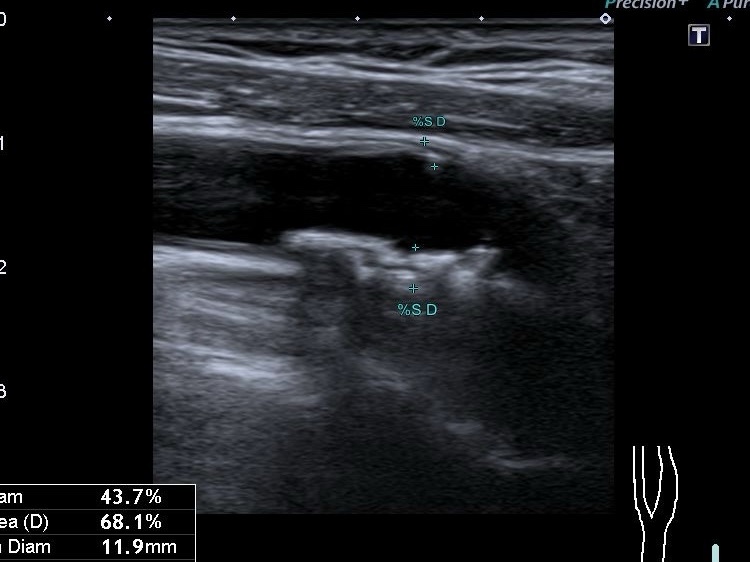

Різниця між 2 та 3 категоріями полягає в товщині стінки: якщо максимальна товщина стінки в місці бляшки до 3 мм — це 2 тип, якщо більше 3 мм — 3 тип. 2 категорія АСБ вважається категорією з низьким ризиком інсультів.

Порада від лікаря: Знати тільки відсоток стенозу (звуження) судини — недостатньо. Важливо розуміти “якість” бляшки. Навіть невелика, але нестабільна бляшка може бути небезпечнішою за велику стабільну.